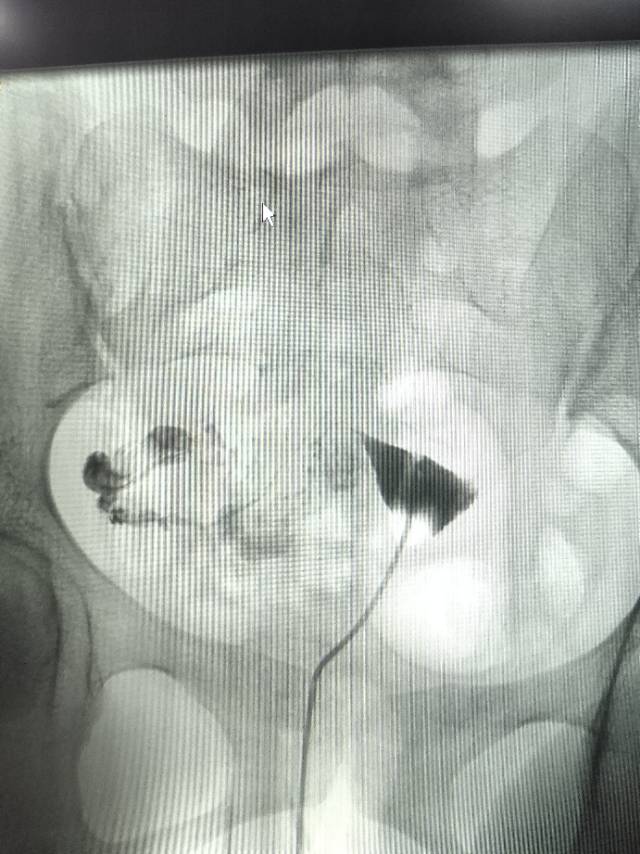

这种必须做手术么还是取了胚胎不是非要做

这个手术不是非得要马上做,需要根据你的年龄、生育计划等来综合评估并权衡利弊后再决定是否需要手术以及什么时候做。如果是做试管通常为了避免输卵管积液及炎症因子逆流至宫腔影响胚胎着床等,会行输卵管结扎等手术,这个手术通常在移植前完成